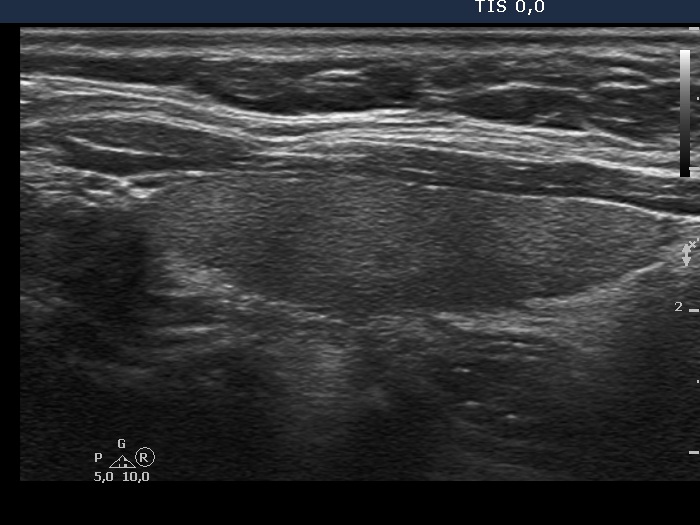

6 months after initial investigation (ultrasonographic picture 5)

Left lobe, longitudinal view.